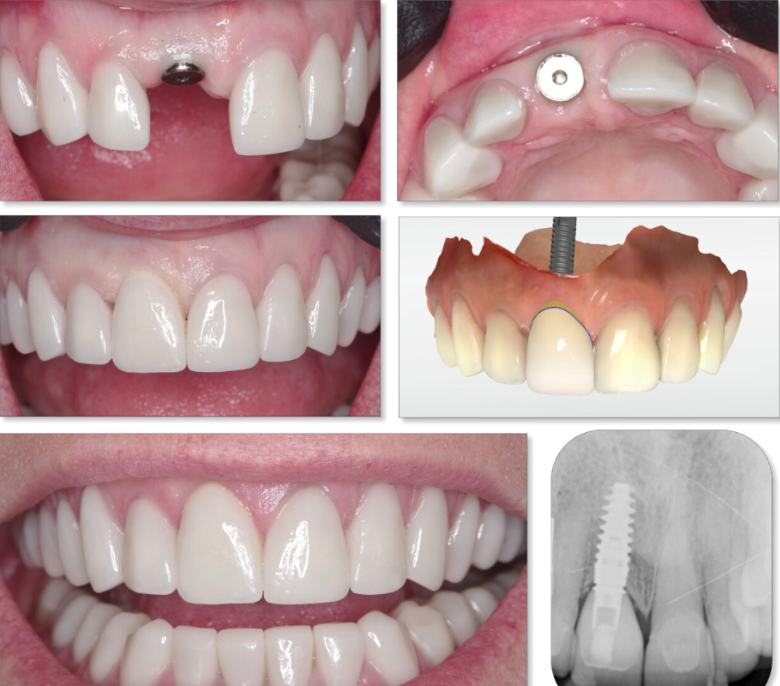

Theo thống kê tại Nha khoa Đông A, hơn 95% khách hàng hài lòng sau khi cấy ghép trụ Implant Tekka, đặc biệt là về tính ổn định và độ thẩm mỹ. Các bác sĩ cũng đánh giá cao khả năng tích hợp xương nhanh, thao tác lâm sàng dễ dàng và tỷ lệ thành công gần như tuyệt đối sau phục hình.

Nha khoa uy tín sử dụng trụ Tekka Pháp

Nha khoa Đông A là một trong những đơn vị tiên phong sử dụng Implant Tekka chính hãng nhập khẩu trực tiếp từ Pháp. Đội ngũ bác sĩ giàu kinh nghiệm, trang thiết bị hiện đại, quy trình vô trùng khép kín là những yếu tố bảo đảm sự an toàn và hiệu quả cho khách hàng.